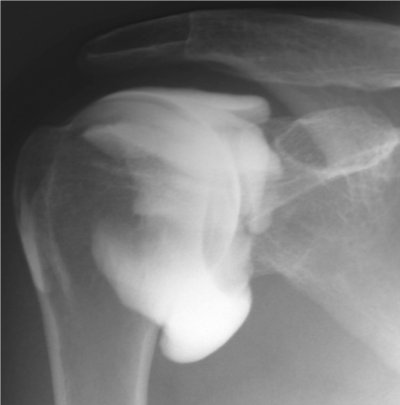

Epaule

Arthrographie de l'épaule

Capsulite rétractile arthrographie (images 1 et 2)

Arthroscanner correspondant (images 3 et 4)